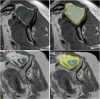

The rotator cuff is a group of four muscles and tendons surrounding the shoulder joint providing it strength and stability. The rotator cuff consists of the subscapularis, supraspinatus, infraspinatus and teres minor. Many shoulder complaints are caused by rotator cuff pathology such as impingement syndrome, tendon tears and other diseases e.g. calcific tendonitis. Diagnosis starts with clinical history and physical examination, after which imaging is often used to help confirm clinical findings depending on the differential diagnosis. The aim of the article is to review the frequently used imaging modalities to assess the rotator cuff and cuff-related disease, specifically focusing on radiography, ultrasonography and magnetic resonance imaging. This article will outline the advantages and disadvantages for each modality and illustrate typical radiological findings of common rotator cuff pathologies.